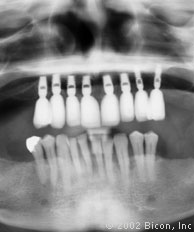

1. | 术前的X光片。 |